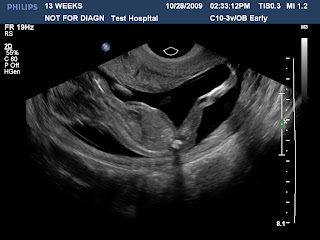

Baby waving at us!

Stretching! Look at those long legs!

Profile

Top view

Yes we had another ultrasound! It was done last week at Philips Healthcare. We feel so incredibly blessed to be able to watch our little baby grow! It is one of the coolest things!

They weren't able to detect what what we are having just yet. But, I'm sure if they called us back in again soon we would for sure know.